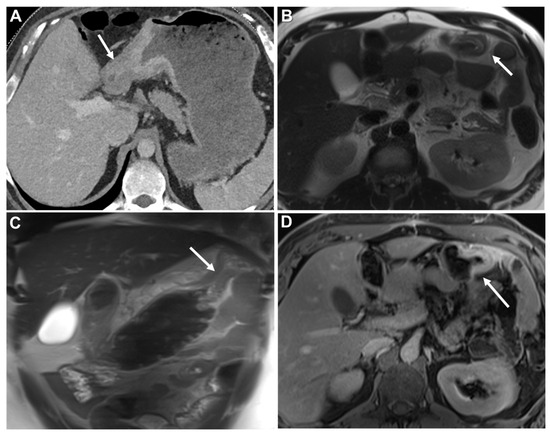

Homogeneous Delayed Enhancement

- Burgain, C.; Germain, A.; Bastien, C.; Orry, X.; Choné, L.; Claudon, M.; Laurent, V. Computed tomography features of gastrointestinal linitis plastica: Spectrum of findings in early and delayed phase imaging. Abdom. Radiol. 2016, 41, 1370–1377. [Google Scholar] [CrossRef]